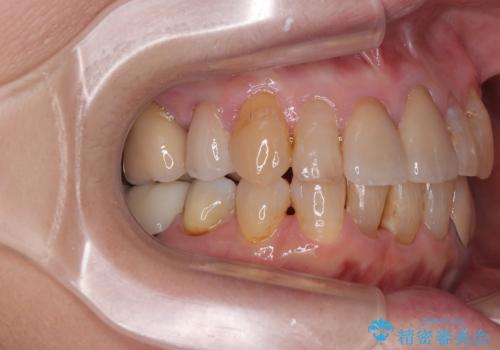

歯肉移植などによる前歯部の歯肉ライン改善を提案しましたが、口を開けたときにほとんど見えないので気にならないとのことで、特に処置を行うことなく補綴治療を行いました。